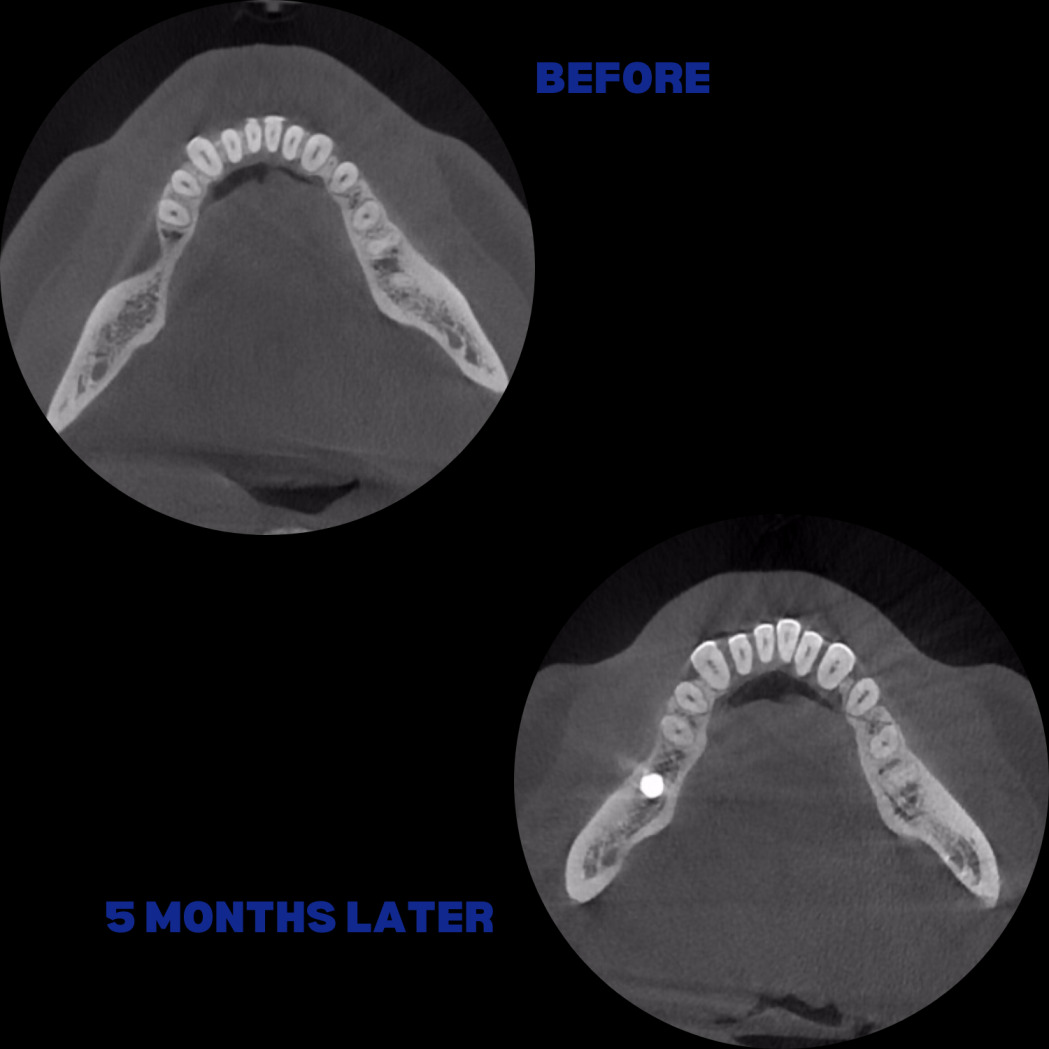

İmplant etrafındaki kemik açıklığını kemik grefti ile tedavi ettiğimiz vakamızdan biri